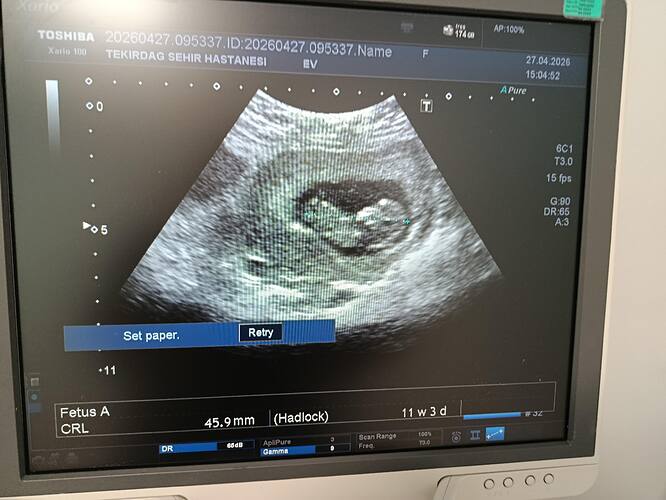

Erkek bebek canım aşağıdan tutunmuş ve kesesi yuvarlak biraz daha büyüsün tekrar atarsin tekrar yorumlarım

Erkek bebek gibi canim

Erkek olabilir

Erkek bebek gibi duruyor canim